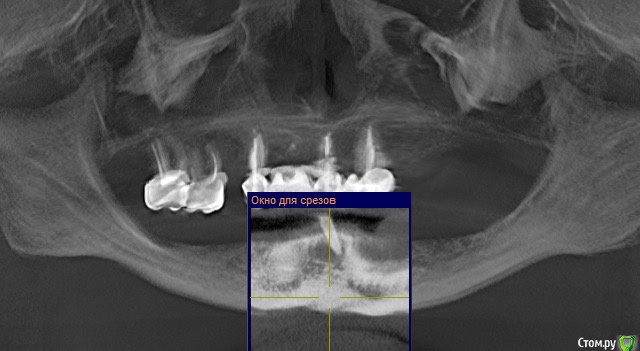

Andre_ Опубликовано 17 марта, 2016 Поделиться Опубликовано 17 марта, 2016 Из анамнеза : Ж, 25 лет, HCv, финансы на зубы лимитированы. Фото 1 до, фото 2 и 3 - около 5 мес. Ортопед хотел/хочет шаровидные абатменты и условно съёмный. Фото во рту утеряно, простит : Биотип тонкий, в позиции 3.3 вместе с шурупом НКР, успешно сьедено, вторичке. Сейчас шея и витки светятся через слизистую. Подвижная слизистая начинается по вершине гребня. Цель - изобразить пкд вокруг имплантов, что посоветуете? Есть смысл углублять преддверие, если да - как? Буду признателен совету, пока план дальнейших действий невразумительный. Ссылка на комментарий

Mane Опубликовано 17 марта, 2016 Поделиться Опубликовано 17 марта, 2016 Сделайте в два этапа. Сначала везде шашлык. Спустя 3 недели - преддверие апикально смещенным лоскутом. Ссылка на комментарий

Andre_ Опубликовано 17 марта, 2016 Автор Поделиться Опубликовано 17 марта, 2016 Спасибо; то бишь, сейчас под расщепленный лоскут Сдт на формирователе, а через месяц - углубить смещенным в области имплантов? Или по всему своду преддверия, в проекции ложа будущего протеза? Ссылка на комментарий